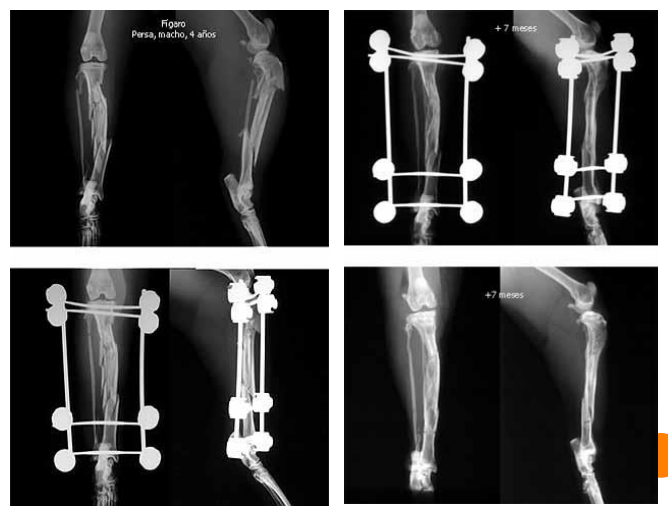

Radiología

- Pérdida de continuidad de la cortical ósea.

- Presencia de líneas radiotransparentes entre segmentos óseos separados.

- Presencia de líneas radiodensas cuando los fragmentos están comprimidos, impactados o superpuestos.

- Al menos dos proyecciones anguladas 90°.

Radiología fracturas

(Imagen en diapositiva)